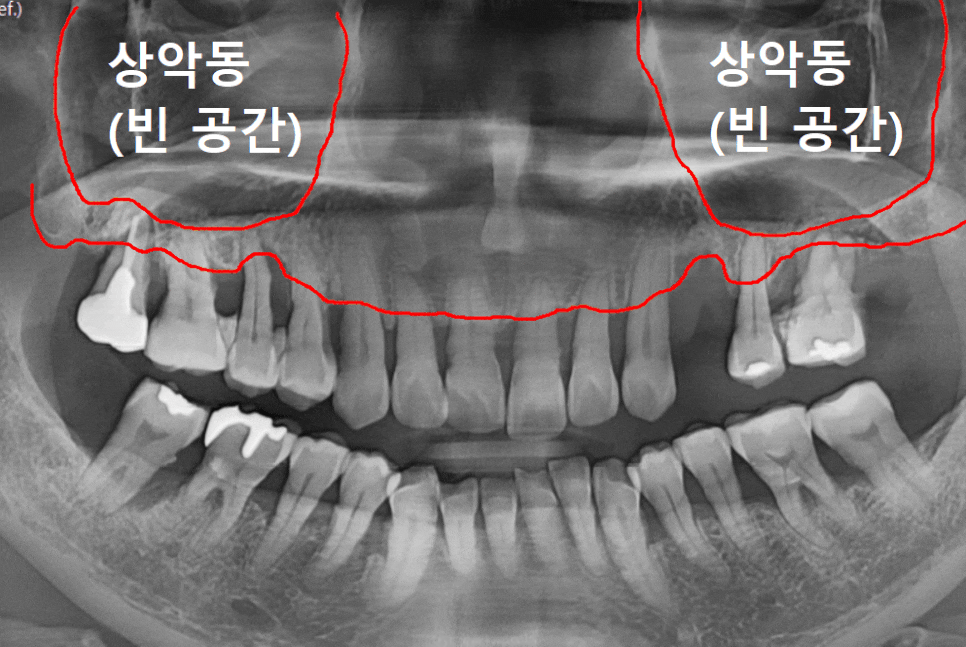

우리 윗니와 광대 사이에는

'상악동'이라는 비어 있는 공기 주머니가 있습니다.

잇몸뼈가 녹아 임플란트를

심을 공간이 부족해지면,

이 상악동의 얇은 막을 살짝 들어 올려

그 공간에 뼈를 채워 넣어야 합니다.

먼저 전체적인 상태를 보기 위해

파노라마 사진을 찍어보았습니다.

보시면 오른쪽 위 어금니(#16)는

뼈 흡수가 한눈에 봐도

심각하게 진행된 모습입니다.

그런데 그 뒤에 있는 치아인 #17은

앞에 치아에 비해 뼈가 크게 녹아 보이지 않으시죠?